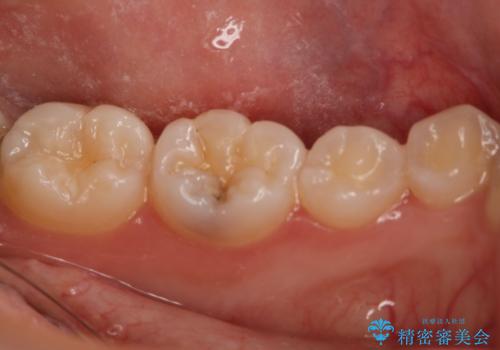

- 10年以上ぶりに歯科に来院された患者です。

口腔内・レントゲン写真からう蝕が見られたので治療を勧めたところ、自費治療を希望されたのでセラミックインレーにて治療を行いました。

左下6番のカリエス除去を行ったところ、深くまで削る必要があったため、CR裏層をした上でセラミックインレー形成をしました。